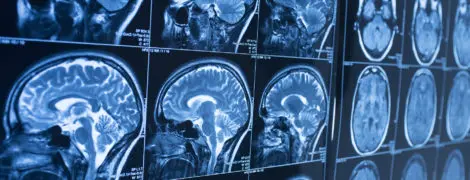

The brain is the most complex organ in the human body. When something goes wrong, our team of multidisciplinary UW Medicine experts can address the issue with research-informed care across four hospitals — Harborview Medical Center, UW Medical Center, Seattle Children’s Hospital and the VA Puget Sound.

Your generous support helps us treat more patients with brain and nervous system disorders, including stroke, epilepsy, Alzheimer’s disease and other types of dementia, Parkinson’s disease and headaches.